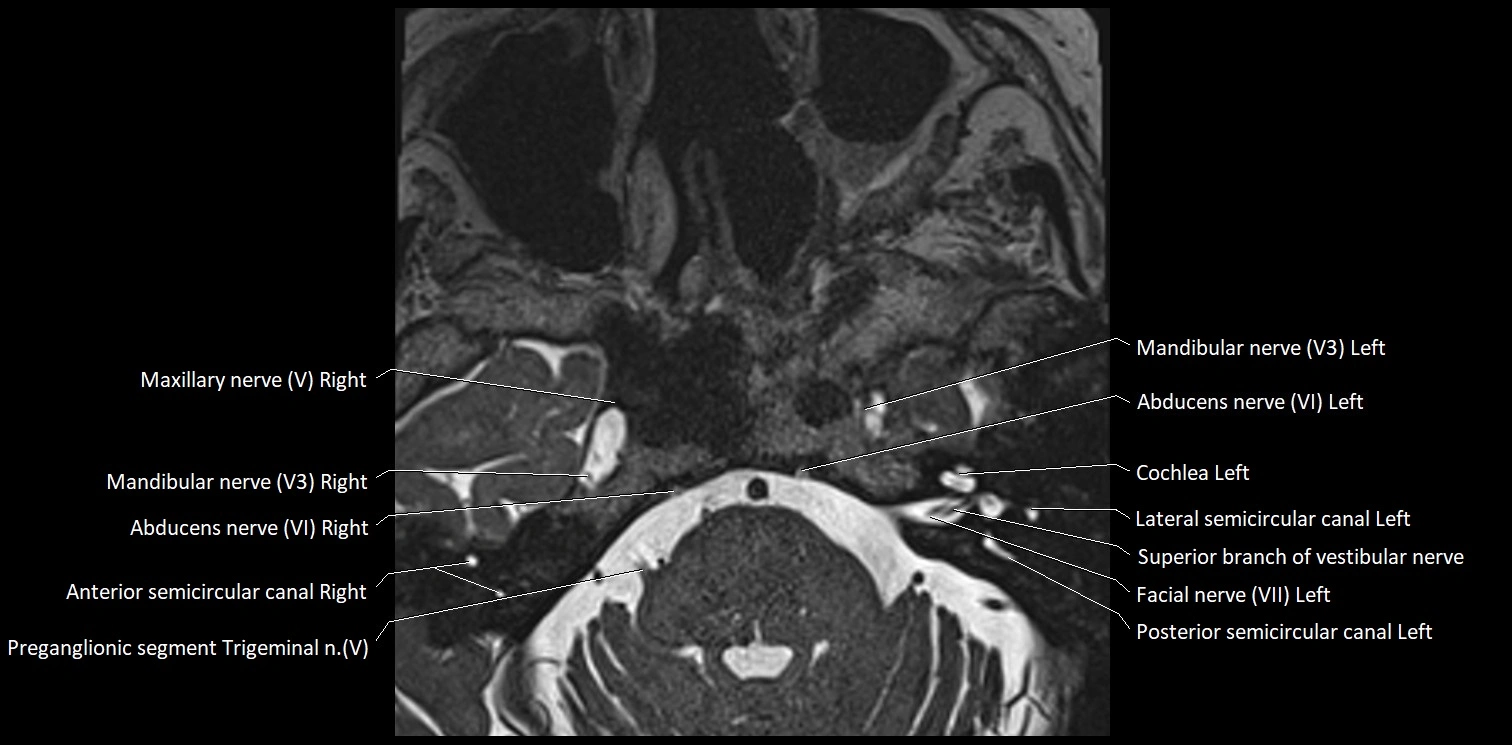

MRI Appearance

• The abducens nerve is a small, thin, linear structure

• Best visualized on high-resolution T2-weighted 3D MRI sequences (e.g., FIESTA or CISS)

• Seen as a hypointense (dark) line running from the brainstem at the pontomedullary junction, traversing the prepontine cistern, and entering Dorello’s canal under the petrosphenoidal ligament, then into the cavernous sinus, and finally the orbit

• May be challenging to visualize in standard MRI due to its small size

• Pathology may be inferred by absence, displacement, or enhancement of the nerve

MRI images

image